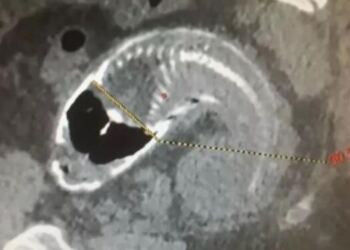

Αυτή η γυναίκα ήταν έγκυος για τα τελευταία 14 χρόνια…Η ιστορία της ξεκινάει από όταν ήταν 13 χρονών! Δεν θα το πιστεύετε!

Αυτή η γυναίκα είναι έγκυος για τα τελευταία 14 χρόνια και ξεκινάει ήδη από όταν ήταν 13 χρονών. Θα πάθετε ...